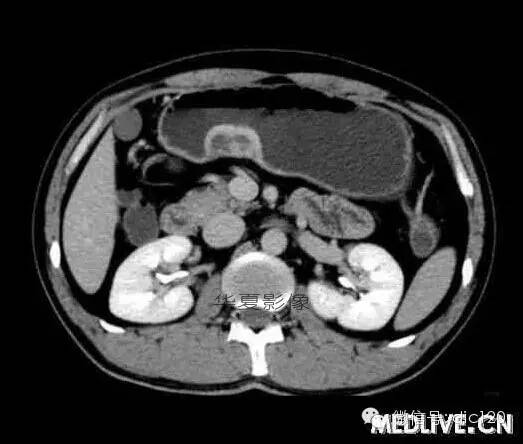

男,36歲,間斷性返酸噯氣3年,3個(gè)月前出現(xiàn)上腹疼痛,饑餓時(shí)加重。圖1-3為CT平掃,圖4-6分別為CT增強(qiáng)掃描的動(dòng)脈期、門脈期和延遲期。

CT檢查可見胃幽門前區(qū)胃小彎側(cè)胃壁局限性增厚、隆起或伴凸向胃腔內(nèi)的小結(jié)節(jié)灶,寬基地,境界光整,注射對(duì)比劑,增強(qiáng)掃描后,CT值可達(dá)50HU以上,與正常胰腺?gòu)?qiáng)化相仿。

胃迷走胰腺大多位在距幽門1-6cm的胃竇胃大彎側(cè),粘膜下層內(nèi),為1-3cm大小的病灶。 與胃壁以寬基底相,增強(qiáng)掃描病灶表面覆蓋的黏膜明顯強(qiáng)化且連續(xù),病灶內(nèi)無(wú)明顯壞死,病變強(qiáng)化方式類似于正常胰腺組織;當(dāng)病灶出現(xiàn)邊緣臍凹征或中央導(dǎo)管征時(shí),對(duì)EP的診斷具有一定的特異性。